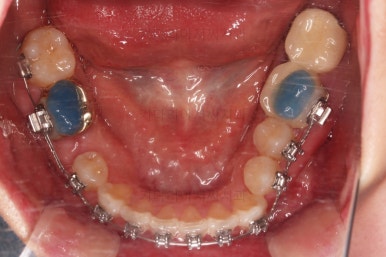

부산치과교정 키다리아저씨치과 초진 시 입안의 모습입니다.

확연히 좌우의 삐뚤어진 정도가 차이나죠.

덧니도 좌측(사진에서 보면 오른쪽) 위아래만 있는 상태고요.

좌측으로 삐뚤어져서 앞니도 좌측으로 쏠려 있는 상태였습니다.